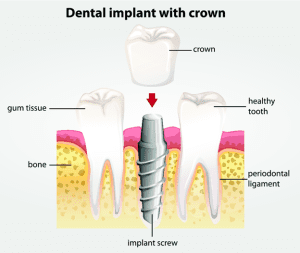

ایمپلنت های دندانی از یک پیچ تیتانیومی تشکیل شده اند که با جراحی درون استخوان فک قرار داده می شوند و یک تکیه گاه قابل مشاهده از لثه بیرون زده است. یک روکش پرسلن با ظاهر دندان طبیعی به این اباتمنت متصل شده است و قسمت قابل مشاهده ایمپلنت را تکمیل می کند. ایمپلنت تیتانیومی تعبیه شده در فرآیندی به نام اسئواینتگریشن با استخوان فک جوش می خورد. این یک تکیه گاه بسیار پایدار برای دندان جایگزین ایجاد می کند. ایمپلنت ها می توانند جایگزین دندان های تکی شوند یا از بریج های ثابت و پروتزهای متحرک از طریق سیستم های اباتمنت چند واحدی پشتیبانی کنند. آنها در مقایسه با بریج ها و پروتزهای معمولی حجم استخوان را حفظ می کنند. تحریک ناشی از جویدن از تحلیل استخوان فک جلوگیری می کند. ایمپلنت ها طی ۱۰ تا ۱۵ سال با شرایط مطلوب، میزان موفقیت بالایی در حدود ۹۵ درصد دارند. این باعث می شود آنها به یک راه حل دائمی قابل اعتماد تبدیل شوند.

ایمپلنت دندانی ساختاری است که می تواند به جایگزینی دندان از دست رفته کمک کند. خود ایمپلنت در داخل یا روی استخوان فک شما قرار می گیرد و به عنوان ریشه مصنوعی دندان عمل می کند. یک دندان مصنوعی به نام روکش به ایمپلنت متصل می شود. به طور کلی، ایمپلنت دندانی به گونه ای طراحی شده است که به عنوان یک پایه دائمی در دهان شما باشد. در واقع، مطالعات میزان موفقیت ۹۰ تا ۹۵ درصدی ایمپلنت های دندانی را در یک دوره ۱۰ ساله گزارش کرده اند. بسیاری از ایمپلنت های دندانی ۲۰ سال یا بیشتر دوام می آورند. با این حال، ممکن است ایمپلنت دندانی در ماه ها یا سال ها پس از قرار دادن آن شکست بخورد. عوامل متعددی وجود دارند که می توانند در این امر نقش داشته باشند.

با این حال ممکن است عمر روکش کوتاه تر از خود ایمپلنت باشد. یک روکش و اباتمنت را می توان چند ماه پس از قرار دادن ایمپلنت، زمانی که زمان کافی برای پیوند با استخوان داشته باشد، به آن متصل کرد. اباتمنت، پایه ای است که به ایمپلنت متصل می شود و از لثه عبور می کند تا روکش به آن متصل شود. تحقیقات نشان می دهند که 50 تا 80 درصد روکش ها 15 تا 20 سال دوام می آورند. علت این است که روکش روزانه دچار ساییدگی و فرسایش می شود، بنابراین آسیب پذیرتر از خود ایمپلنت است. هزینه روکش بسیار کمتر از ایمپلنت است و تعویض آن آسان تر است.

ایمپلنت های دندانی قرار است دائمی باشند. دلیل این امر این است که آنها مستقیماً با استخوان فک در تماس هستند و از طریق فرآیندی به نام اسئواینتگریشن با بافت استخوان اطراف پیوند می خورند. هنگامی که اسئواینتگریشن کامل می شود، ماده ایمپلنت و استخوان اطراف آن جوش خورده اند. به همین دلیل، ایمپلنت می تواند به عنوان ریشه دندان مصنوعی عمل کند و پایه محکمی برای دندان مصنوعی تشکیل دهد. در حالی که خود ایمپلنت به گونه ای طراحی شده است که دائمی باشد، ممکن است روکش متصل به آن به دلیل ساییدگی و فرسایش طبیعی به تعویض نیاز داشته باشد. حدود ۵۰ تا ۸۰ درصد روکش ها ممکن است در ۱۵ تا ۲۰ سال به تعویض نیاز داشته باشند.